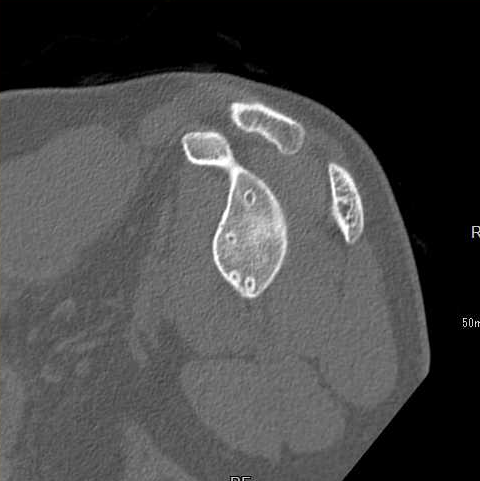

CT撮影

CT検査(Computed Tomography:コンピュータ断層診断装置) CT検査は、X線を使って身体の断面を撮影する検査です。骨折の部位の特定、転位(骨のずれ方)など判断できます。